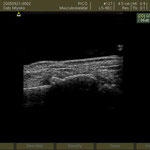

○肘頭骨折

肘を着いて転倒 超音波検査で骨折が確認できたので病院を紹介しました。

肘の頭と書きますが、ここが折れると手術摘要です。筋肉の影響で骨折した部分が離れようとするからです。

手術後は当院に通ってもらい肘に超音波をかけました。超音波の微量な刺激を骨折部分に当てると骨の癒合が早まると見直されています。 同時に温熱療法 マッサージも施しました。予後は大変良かったです。